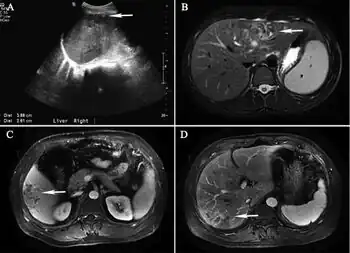

As to the diagnosis of Hepatic capillariasis the epidemiological history, and clinical manifestations, are taken into account as well as:[4]

- Ultrasound

- MRI

- Liver tissue biopsy